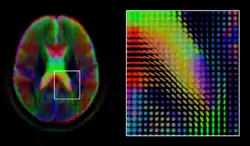

Diffusion MRI

Diffusion MRI is a structural magnetic resonance imaging modality that allows measurement of the diffusion process of molecules. Diffusion is measured by applying a gradient pulse to a magnetic field along a particular direction. In a typical acquisition, a set of uniformly distributed gradient directions is used to create a set of diffusion weighted volumes. In addition, an unweighted volume is acquired under the same magnetic field without application of a gradient pulse. As each acquisition is associated with multiple volumes, diffusion MRI has created a variety of unique challenges in medical image computing.

In medicine, there are two major computational goals in diffusion MRI:

The diffusion tensor,[58] a 3 × 3 symmetric positive-definite matrix, offers a straightforward solution to both of these goals. It is proportional to the covariance matrix of a Normally distributed local diffusion profile and, thus, the dominant eigenvector of this matrix is the principal direction of local diffusion. Due to the simplicity of this model, a maximum likelihood estimate of the diffusion tensor can be found by simply solving a system of linear equations at each location independently. However, as the volume is assumed to contain contiguous tissue fibers, it may be preferable to estimate the volume of diffusion tensors in its entirety by imposing regularity conditions on the underlying field of tensors.[59] Scalar values can be extracted from the diffusion tensor, such as the fractional anisotropy, mean, axial and radial diffusivities, which indirectly measure tissue properties such as the dysmyelination of axonal fibers [60] or the presence of edema.[61] Standard scalar image computing methods, such as registration and segmentation, can be applied directly to volumes of such scalar values. However, to fully exploit the information in the diffusion tensor, these methods have been adapted to account for tensor valued volumes when performing registration [62][63] and segmentation.[64][65]

Given the principal direction of diffusion at each location in the volume, it is possible to estimate the global pathways of diffusion through a process known as tractography.[66] However, due to the relatively low resolution of diffusion MRI, many of these pathways may cross, kiss or fan at a single location. In this situation, the single principal direction of the diffusion tensor is not an appropriate model for the local diffusion distribution. The most common solution to this problem is to estimate multiple directions of local diffusion using more complex models. These include mixtures of diffusion tensors,[67] Q-ball imaging,[68] diffusion spectrum imaging [69] and fiber orientation distribution functions,[70][71] which typically require HARDI acquisition with a large number of gradient directions. As with the diffusion tensor, volumes valued with these complex models require special treatment when applying image computing methods, such as registration[72][73][74] and segmentation.[75]